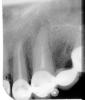

Bier Опубликовано 31 июля, 2009 Поделиться Опубликовано 31 июля, 2009 причина в плохо-пролеченном канале. Там выросла гранулема.обзорный снимок и есть ортопантомограмма. Ссылка на комментарий

Bier Опубликовано 8 августа, 2009 Поделиться Опубликовано 8 августа, 2009 врач ваш не хочет снимать коронки и переделывать их за свой счет. у вас там полупустой канал, в нем живут микробы, канал надо вычистить иначе делай резекцию или не делай толку не будет. 1 Ссылка на комментарий